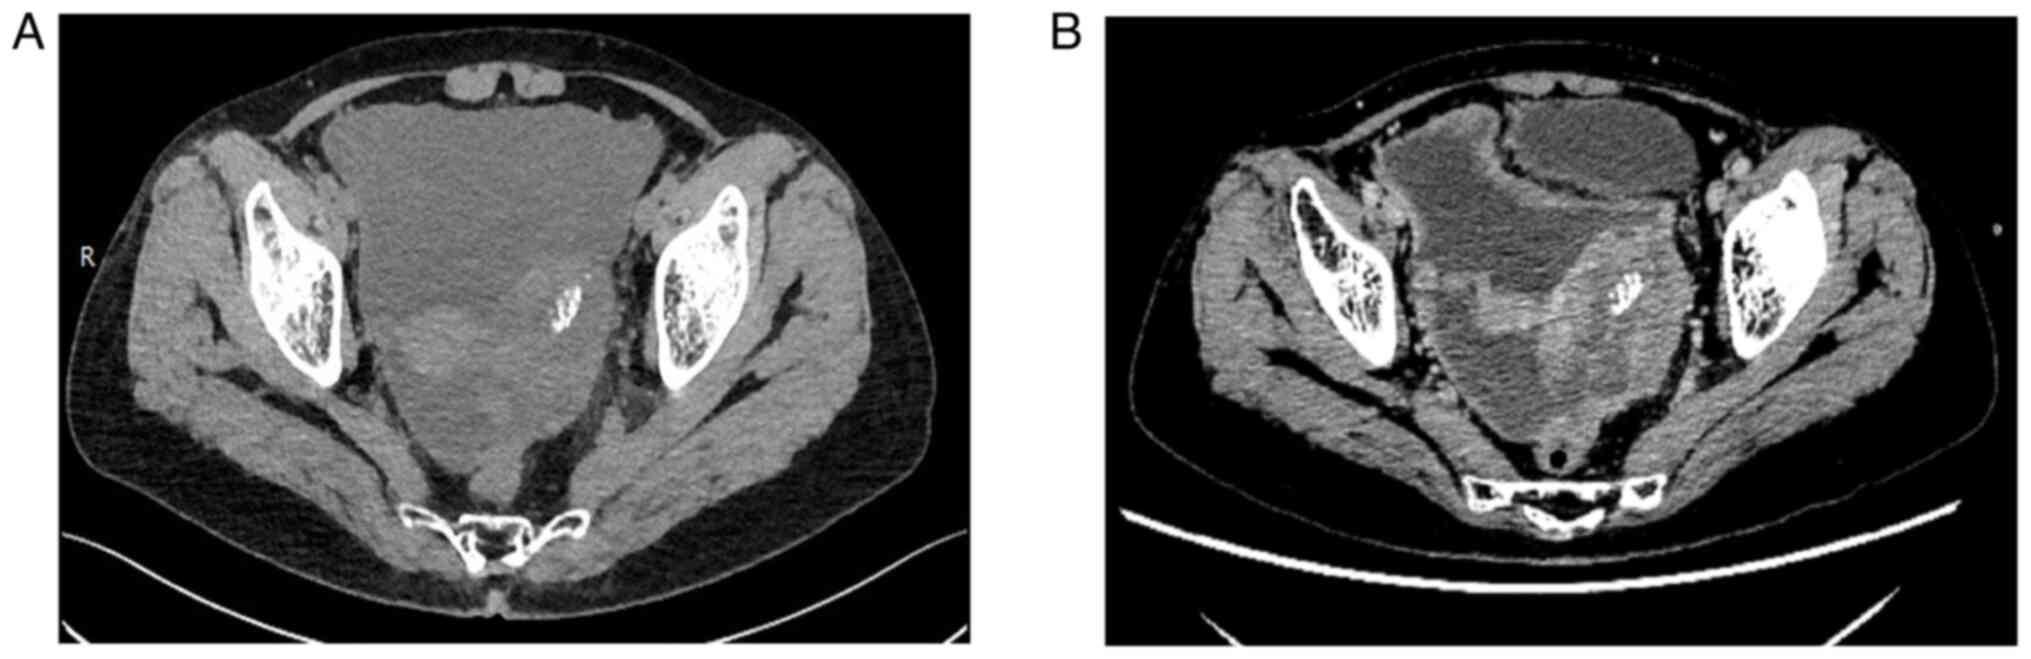

SMARCA4‑deficient uterine adnexal tumor with ascites: A case report and literature review

SWI/SNF‑related matrix‑associated actin‑dependent regulator of chromatin subfamily A member 4 (SMARCA4)‑deficient tumors are rare and highly aggressive tumors characterized by a loss of SMARCA4 expression, and SMARCA4‑deficient tumors in the adnexal area of the uterus are particularly rare. The present study describes the case of a 64‑year‑old woman who was admitted to Weifang People's Hospital (Weifang, China) with abdominal distension, and was observed to have a mass with ascites in the adnexal area of the uterus. Based on clinical, imaging and pathological findings, the patient was diagnosed with a SMARCA4‑deficient adnexal tumor with ascites. Biopsy of the left and right adnexal lesions was performed, and the patient was administered chemotherapy. After one cycle of bevacizumab, sindilizumab and carboplatin, no further treatment was administered. After biopsy and chemotherapy, the abdominal distension was alleviated and the general condition of the patient was satisfactory. The patient was followed up and died 3 months after treatment. Notably, it is important to avoid misdiagnosing this tumor as other types of adnexal uterine tumors, and morphological and immunohistochemical features may be useful for diagnosing primary SMARCA4‑deficient tumors in the adnexal area of the uterus.

Figure 1